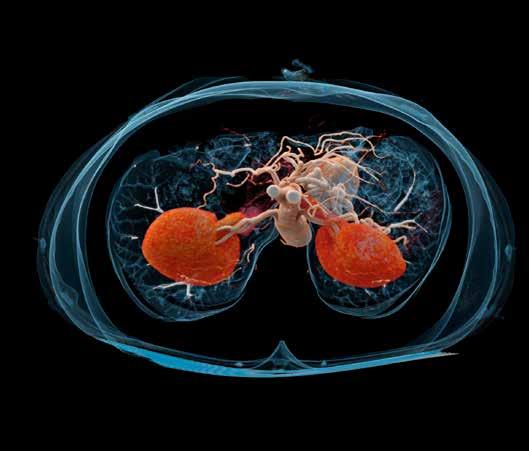

– Og den kan brukes til alt, MSK, nevro, hjerte, abdomen, og så videre, sier Svendsmark og legger til:

En bruk man kan se for seg for denne maskinen i land som Norge, sier produktspesialisten, er til lunge-MR.

– Det har ikke vært mulig før, fordi luft ikke har nok hydrogen til at man får signaler.

Men med så lav Tesla-styrke kan man detektere lungevev.

– Kanskje gjør denne at man kan erstatte CT thorax med MR av astmabarn som følges opp gjennom livet, men det er et område som må utforskes litt, sier Svendsmark.